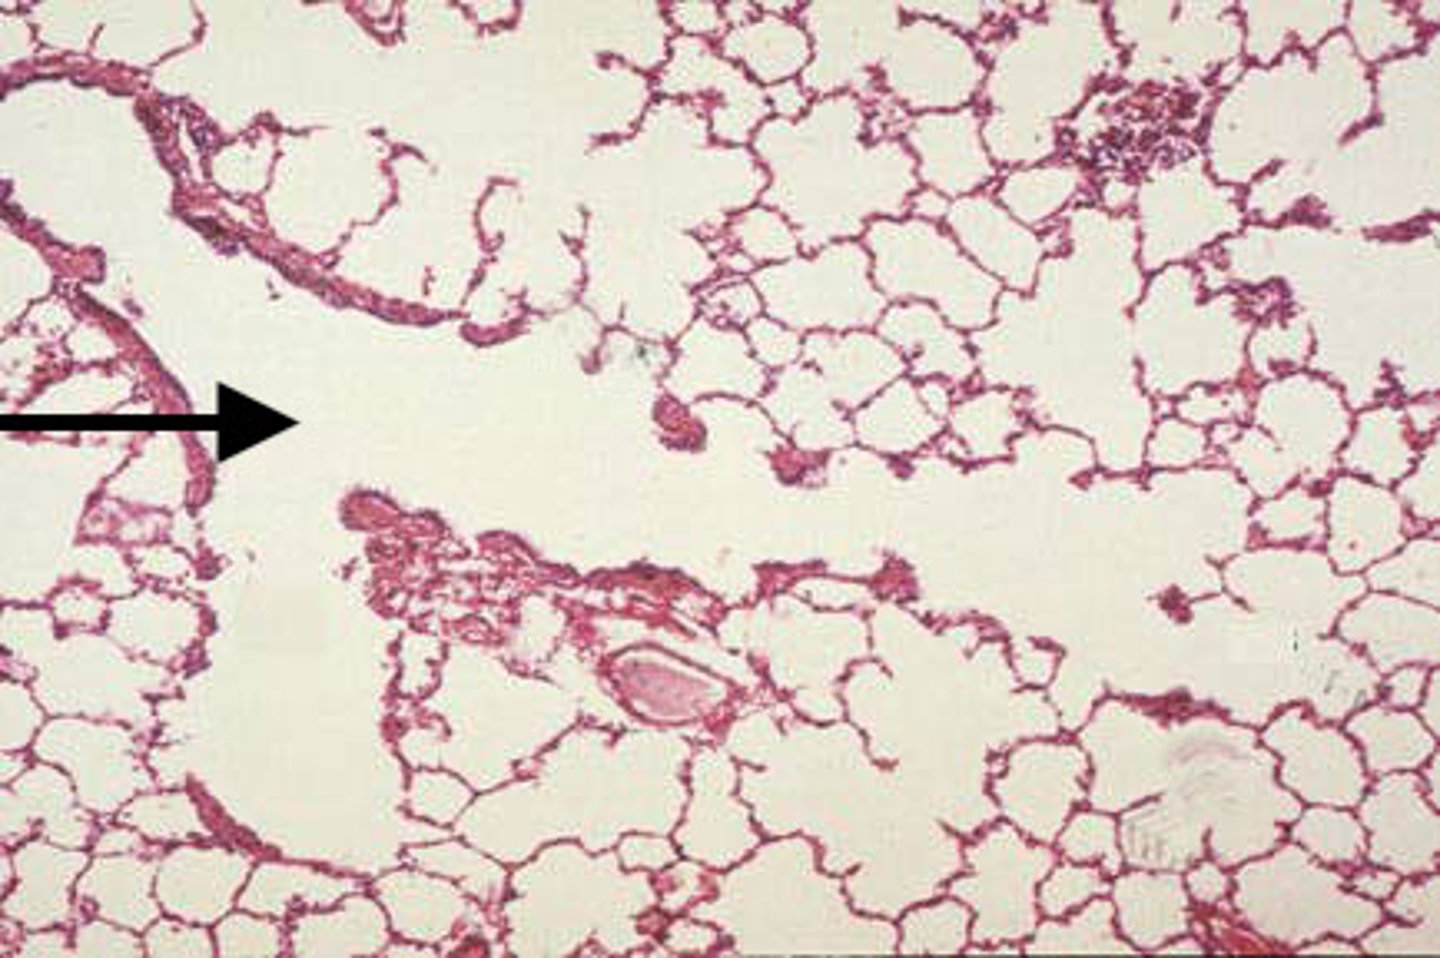

aveolar duct

Identify the organ indicated by the arrow.